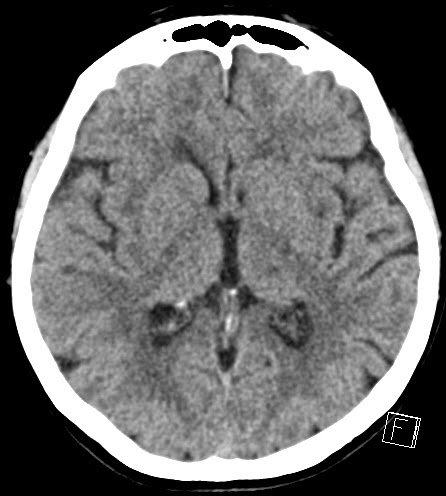

| ventrolateral left thalamic infarction related to the symptoms (appropriate windowing of the basal ganglia) |